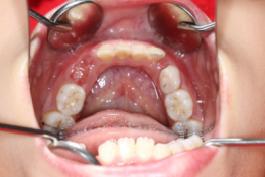

❸ 牙齿不齐:影响咬合关系,影响美观。

前

后